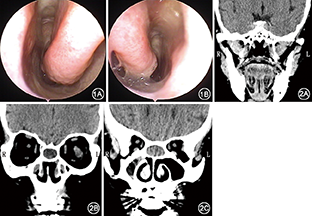

患者女,50岁。因自幼无嗅觉伴反复头痛、流脓涕30余年于2015年9月1日到黄陵县人民医院耳鼻咽喉科门诊就诊。患者自幼无嗅觉,近30余年反复出现头部胀痛,以双侧眉弓、鼻根部及眉间为主,呈持续性隐痛伴头昏、流脓涕,给予抗感染治疗后症状改善,无头晕、眼花、恶心、呕吐,无鼻塞,未见发热、眼痛,无复视。患者无青光眼及高血压病史。鼻内镜检查:双侧下鼻甲不大,无中鼻甲、上鼻甲及嗅裂;无钩突、筛泡及筛漏窦等结构,鼻腔未见新生物和异常分泌物(图1)。CT检查示:双侧筛窦融合为一个窦腔,内充满软组织密度影,双侧额窦较小,有炎性组织,蝶窦气化差(图2)。给予丙酸氟替卡松喷鼻、桃金娘油肠溶胶囊口服及抗生素治疗,15 d后患者门诊复查临床症状明显好转,由于患者的经济原因,拒绝手术及进一步检查。

在各鼻窦的异常发育或变异中,以额窦常见,其次为蝶窦、上颌窦,而筛窦的变异极少见[1]。在本例中,患者以鼻根部及眉间持续性隐痛、流脓涕、嗅觉丧失及反复溢泪的病史来就诊;根据鼻内镜检查及CT结果发现,患者额窦、筛窦、蝶窦及上颌窦的发育均有不同程度的异常,以筛窦及蝶窦的发育异常最为明显。由于鼻腔内的大部分结构是由胚胎时期原始筛骨上的筛甲突形成的,所以筛骨发育严重异常可导致鼻腔结构明显异常,甚至中鼻甲以上结构缺失,当筛板缺失可致嗅觉丧失。本例同时伴有多个鼻窦畸形的情况在临床上极少见。高分辨鼻窦CT是诊断鼻窦畸形的主要手段,尤其是鼻窦骨窗CT影像。部分鼻窦畸形或异常患者经相应的手术或药物治疗后,症状可缓解或消失。